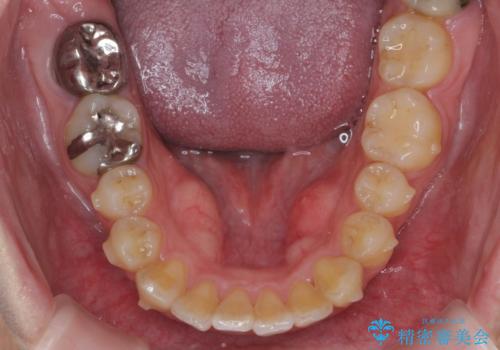

歯を抜かずに行う前歯の角度の改善

- 歯を抜かずに前歯の角度を改善したい、と矯正治療を希望され来院されました。

可及的に前歯部にIPR(歯間の削合)を行い、抜歯をせずマウスピース矯正システムインビザラインで歯の排列を行っていく治療計画としました。

治療の前後を比べると、がたつきや歯の角度が改善したことがしっかりと確認されました。